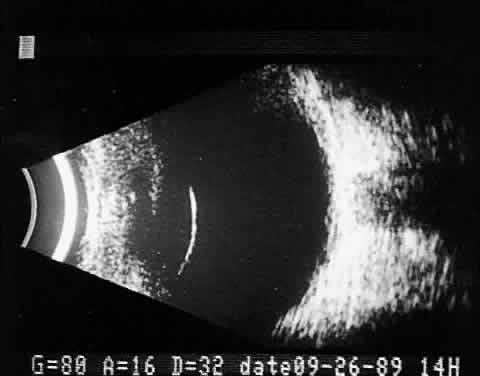

Recent improvements in computer technology and digital B-scan devices have permitted the development of tomographic (3D) static displays. The new devices, often called 3D ultrasound instruments, increase understanding of complex topographic information (Fig. 18). Sophisticated software permits measurements of captured images (linear, area, and volume) as well as surface renderings18,19 (Figs. 19 and 20). Kinetic (real-time) information is not yet available in 3D and continues to be obtained during kinetic B-scan examinations performed before 3D image capture.

Fig. 18. 3D tomographic ultrasonogram software permits a combined tomographic 3D coronal/sagittal view of extensive choroidal detachment involving the anterior and postequatorial regions of the eye.